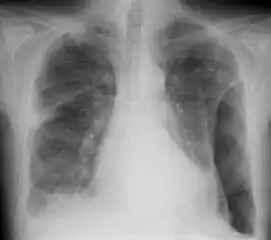

A fibrothorax can typically be diagnosed by taking an appropriate medical history in combination with the use of appropriate imaging techniques such as a plain chest X-ray or CT scan.[1] These imaging techniques can detect fibrothorax and pleural thickening that surround the lungs.[11] The presence of a thickened peel with or without calcification are common features of fibrothorax when imaged.[1] CT scans can more readily differentiate whether pleural thickening is due to extra fat deposition or true pleural thickening than X-rays.[1]

If a fibrothorax is severe, the thickening may restrict the lung on the affected side causing a loss of lung volume.[11] Additionally, the mediastinum may be physically shifted toward the affected side.[1] A reduction in the size of one side of the chest (hemithorax) on an X-ray or CT scan of the chest suggests chronic scarring.[9] Signs of the underlying disease causing the fibrothorax are also occasionally seen on the X-ray.[9] A CT scan may show features similar to those seen on a plain X-ray.[11] Lung function testing typically demonstrates findings consistent with restrictive lung disease.[9]

Chest X-ray showing bilateral fibrosis and pleural thickening in infection with non-tuberculosis mycobacteria.